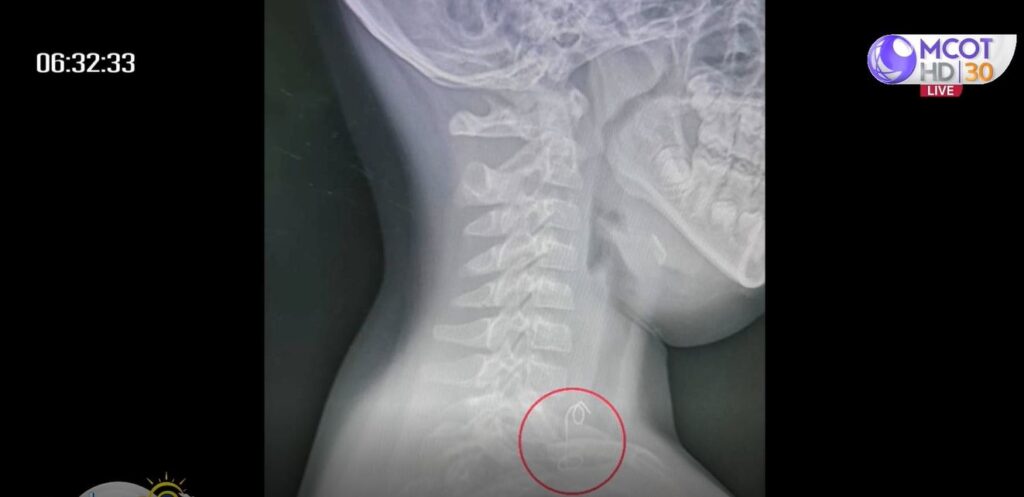

สักพักลูกชายบอกว่าเจ็บคอมาก แม่จึงงงว่าจู่ๆ เจ็บคอได้อย่างไร ตอนนั้นลูกชายถือไม้ไก่ย่างอยู่ในมือ แต่ไม่เหลือเนื้อไก่ย่างแล้ว จึงสงสัยว่าอาจมีกระดูกไก่ติดคอ เมื่อหาน้ำให้ลูกดื่มปรากฏว่ายิ่งมีอาการเจ็บปวดและร้องไห้ดังมาก จึงรีบพาลูกส่งโรงพยาบาล หมอรีบนำตัวลูกชายเข้าห้องฉุกเฉินเพื่อเอกซเรย์ทันที จึงเห็นวัตถุคล้ายขดขวดติดอยู่ที่ส่วนบนของหลอดอาหาร แพทย์ผู้เชี่ยวชาญด้านหู คอ จมูก จึงสั่งผ่าตัดเป็นการด่วน